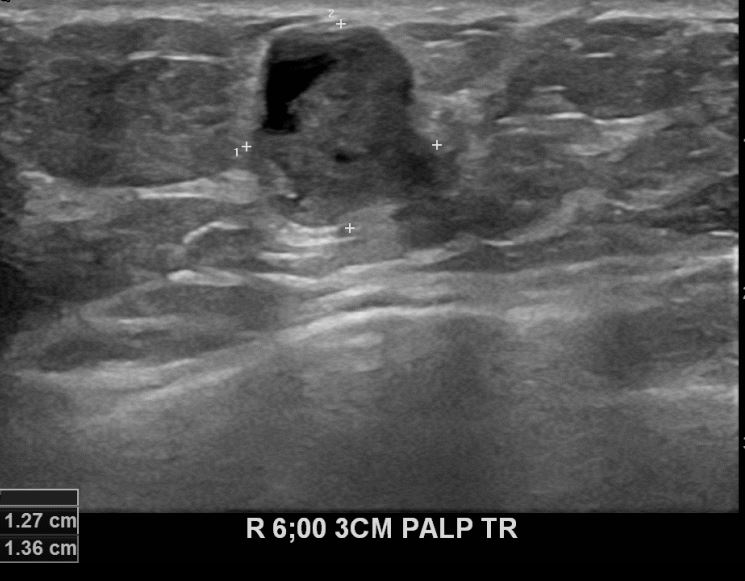

아산유외과 개원후 633번째 유방암진단

상기환자 외부검사상 이상소견으로 내원하신 60대여성으로 우측 유방의 의심스러혹

조직검사시행해 유방암 진단되었읍니다